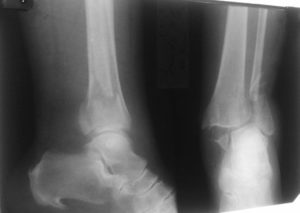

Диагноз перелома лодыжки ставится из совокупности данных опроса, осмотра и диагностики.

Для определения наличия перелома и его характера необходимо провести диагностические исследования, первым из которых является рентгеноскопия. Рентгеновский снимок выполняют в двух проекциях: боковой и передне-задней.

Дополнительными методами исследования сустава является сонография (ультразвуковое исследование), артрография и артроскопия.